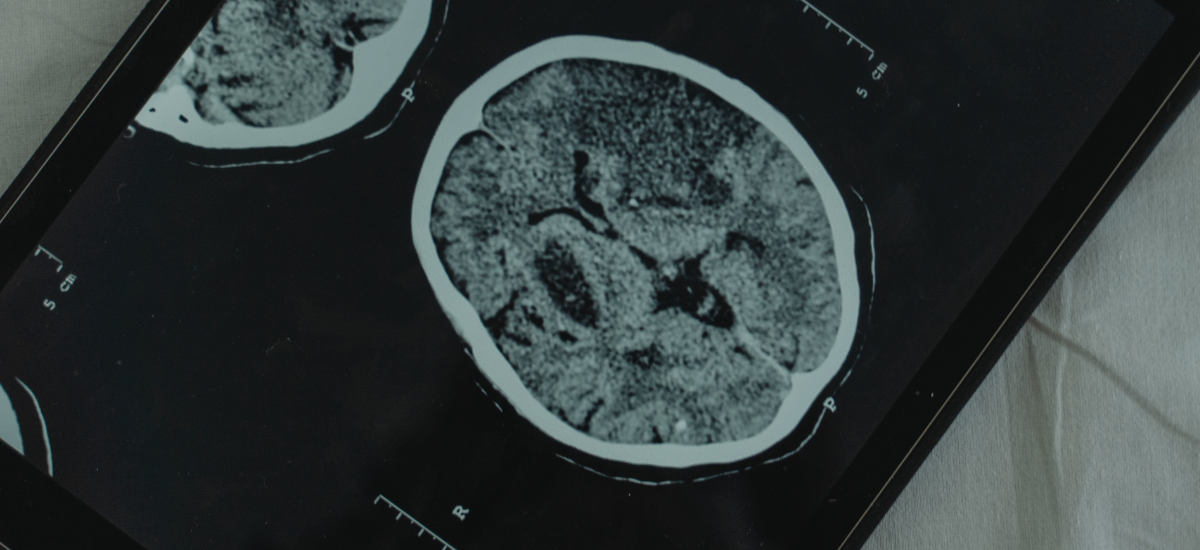

Strokes fall into two main types: ischaemic, which occurs when a blood vessel is blocked, and haemorrhagic, caused by bleeding in the brain.

About 80 per cent of strokes are ischaemic, and while this remained the most common type across all ages, haemorrhagic strokes were relatively more frequent among younger adults, often linked to hypertension, aneurysms or vascular malformations.